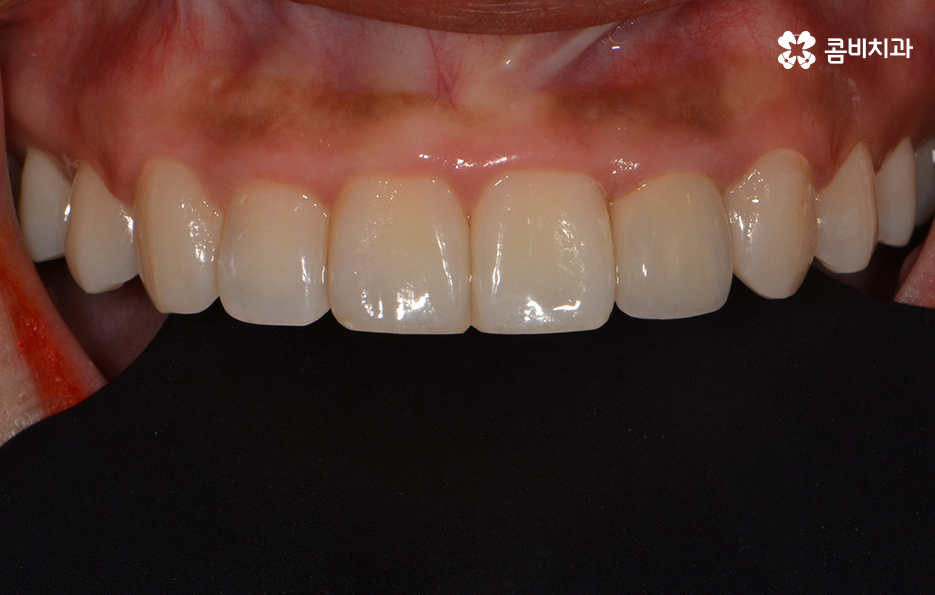

마지막으로 소개드릴 앞니 충치치료 방법은 라미네이트입니다.

충치가 앞니에 발생했을 때 초기에는 레진으로

치료를 하지만 손상이 좀 더 심한 경우 라미네이트를 활용합니다.

라미네이트는 충치 치료 방법보다는 빠른 치아성형 방법으로

많이 알려져 있는데 앞니의 벌어짐, 깨짐 등의 치료에도 많이 쓰입니다.

심미성이 우수하지만 치아의 겉면에 세라믹 박편을

붙이는 방식의 치료 방법이기 때문에

자연치아에 비해 내구성이 약한 편이므로

음식물을 섭취할 때 주의를 하시는 것이 필요합니다.